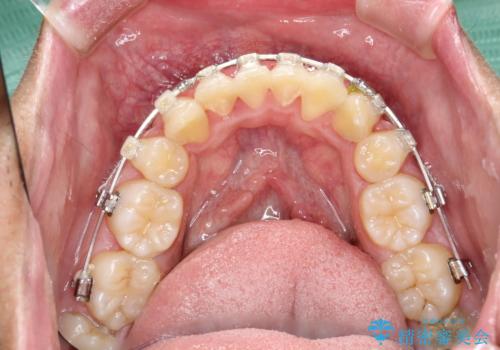

ワイヤー矯正終了時に装置除去と合わせてPMTC

- ワイヤー矯正の終了時にしばらく行っていないためクリーニングも希望されました。装置の除去j時にPMTC60分コースを行いました。

装置を除去すると、エナメル質にダメージがかかることなどがあります。除去の際、一緒にクリーニングを行うことで、エナメル質をなめらかにしたり、歯ぐきの引き締まりが見られます。また、歯ブラシだけでは取り除けない汚れも取り除きますので、歯の表面がツルツルになります。矯正治療中・終了時には合わせてPMTCを行うことがおすすめです。